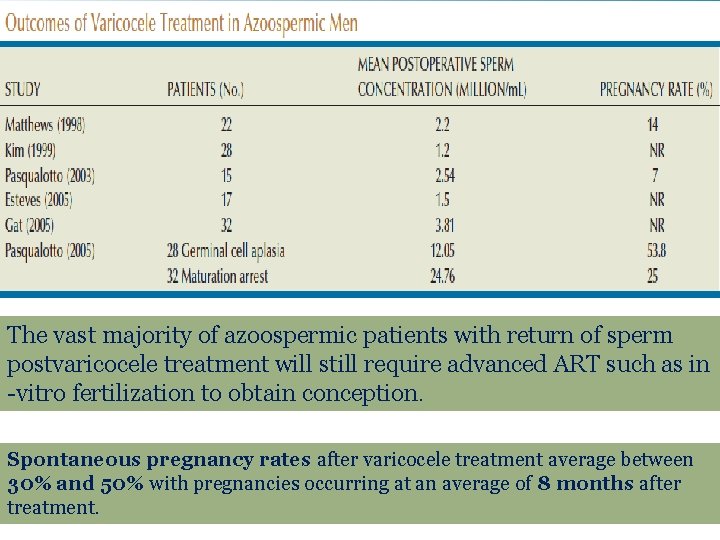

The vast majority of azoospermic patients with return of sperm postvaricocele treatment will still require advanced ART such as in -vitro fertilization to obtain conception. Spontaneous pregnancy rates after varicocele treatment average between 30% and 50% with pregnancies occurring at an average of 8 months after treatment.